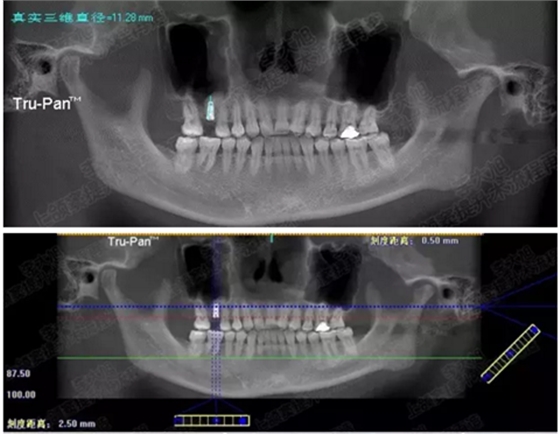

病例四

剩余骨量2mm-5mm且存在斜形竇底

007.png

提升8mm

008.png

009.png